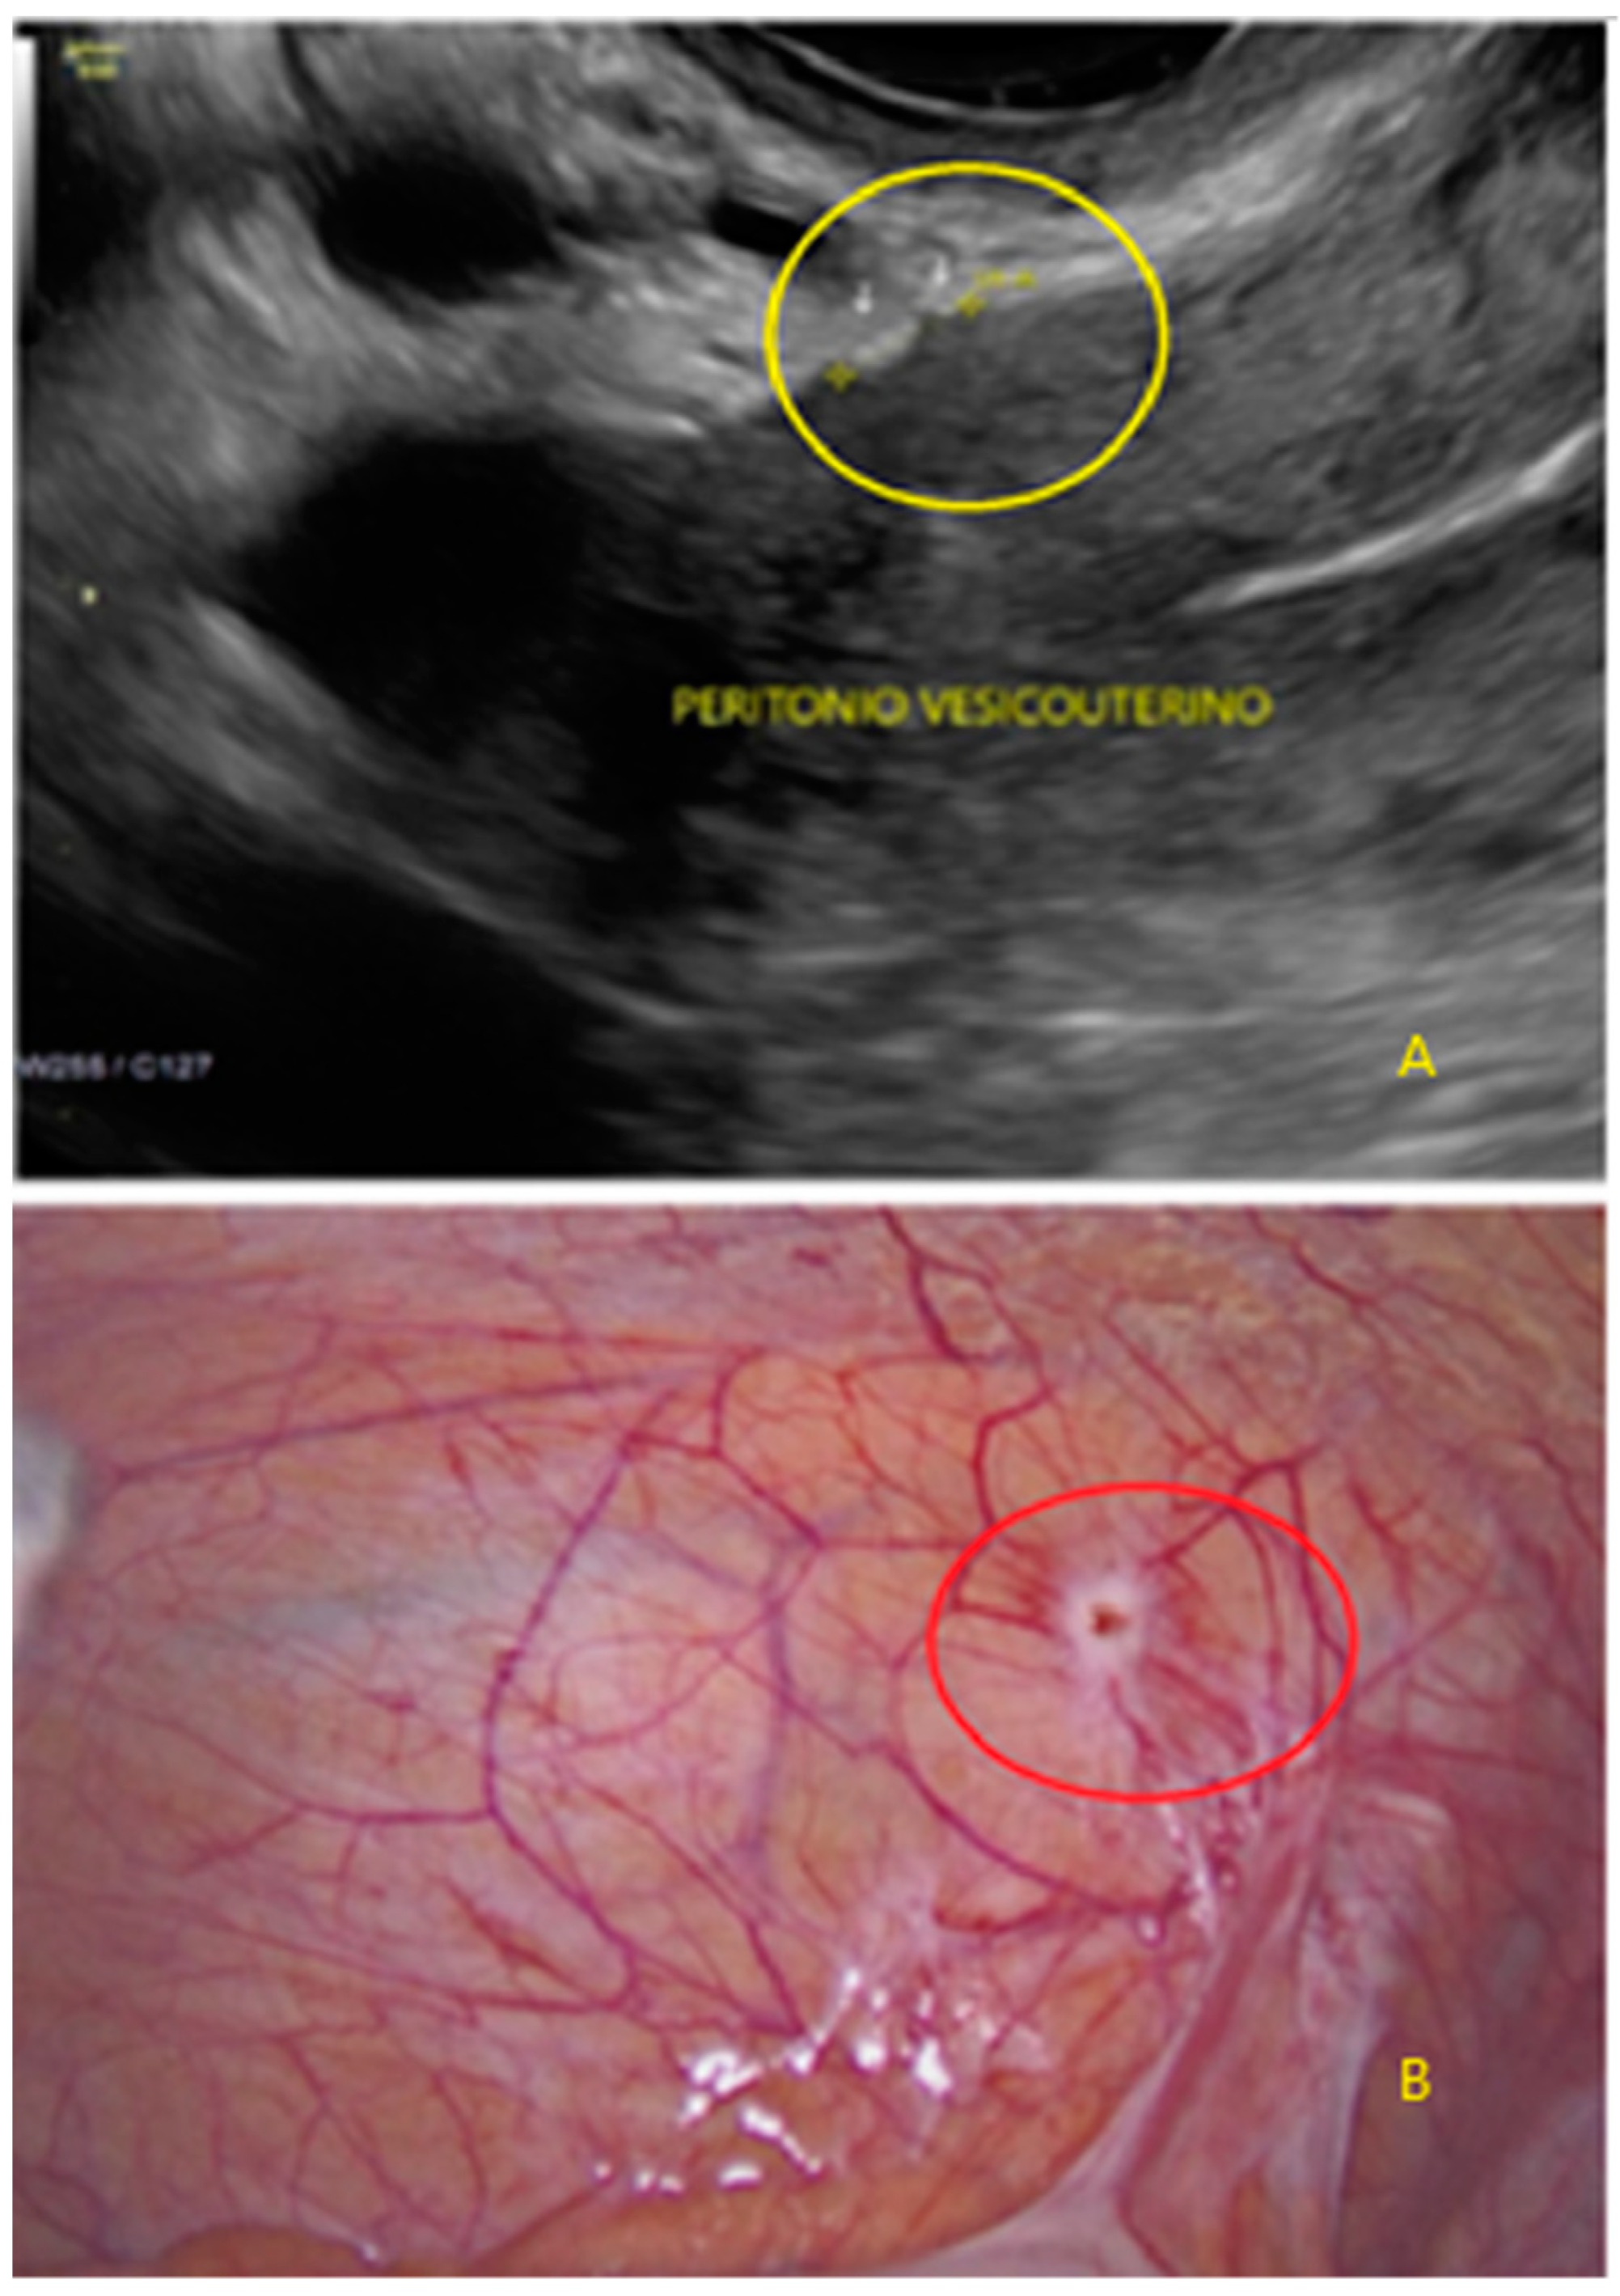

- The presence of hypoechogenic associated tissue (hypoechoic areas surrounding a small cyst area; we called this a “hat”). This tissue does not protrude or invaginate the peritoneal surface.

- The lesion may be convex, protruding from the peritoneal surface into the peritoneal cavity (we called this “bulging”), or it may appear as a concave defect in the peritoneum (we called this a “pocket”).

- The presence of hyperechoic foci (we called this a “pearl”).

- The presence of velamentous (filmy) adhesions associated to the lesion (we called this a “veil”).

3.1. Cystic Solitary Lesion